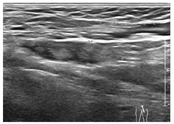

辅助检查:(1)实验室检查:血常规+镜检+CRP:Hb 98 g/L,WBC 9.96×109/L,N 84%,L 8%,单核细胞8%, PLT 83×109/L,CRP 199 mg/L。降钙素原(PCT) 26.11 ng/mL,白细胞介素-6 653.3 ng/mL,乳酸2.22 mmol/L,血沉57 mm/h,铁蛋白367.3 ng/mL,白蛋白20.8 g/L,球蛋白20.6 g/L,谷氨酸氨基转移酶15 U/L,天门冬氨酸氨基转移酶42 U/L,总胆红素11.3 μmol/L,间接胆红素3.6 μmol/L,肌酐35 μmol/L,尿素6 mmol/L。动脉血气分析:pH 7.438,氧分压(PO2)35 mmHg,二氧化碳分压(PCO2)59 mmHg,剩余碱(BE) -0.1 mmol/L。3次血培养均提示金黄色葡萄球菌(其中2次为外院检查,未行药敏试验),我院药敏结果提示苯唑西林敏感。左股骨开窗术中留取骨髓培养提示MSSA。结核菌素试验、γ-干扰素释放试验均阴性。9种呼吸道病原抗体检测阴性,血EB病毒、结核杆菌、肺炎支原体DNA均阴性。凝血酶原时间13.2 s,国际标准化比值1.14,活化部分凝血活酶时间32.3 s,凝血酶时间16 s,纤维蛋白原4.812 g/L,D-二聚体0.8 mg/L。免疫球蛋白及T细胞亚群分析正常。抗核抗体与抗可溶性核抗原抗体均阴性,狼疮抗凝物、抗心磷脂抗体和抗β2糖蛋白抗体(抗β2GP1抗体)均阴性。胸腔积液检查:WBC 858×103/L,RBC 125×106/L,N 43%,L 52%,培养(-)。(2)影像学及功能检查:肺CT示双肺多发磨玻璃影、结节及实变影,部分伴空洞形成,双侧胸腔大量积液(图1A)。肺CT动脉造影(CTPA)示左肺动脉部分分支内多发充盈缺损(图2A)。双下肢MRI示T2WI左侧骨髓腔内斑片状高信号(图3),双下肢血管B超提示左股静脉血栓(大小约50 mm×7 mm),未探及血流信号(图4)。超声心动图未见心脏结构异常及瓣膜赘生物。

DVT在儿童中比较少见,因查体时发现患儿左下肢呈现弥漫性肿胀,完善下肢血管B超证实同时合并DVT。儿童DVT高发年龄段分别为婴儿期(20%)及青春期(50%),总发病率不高,但呈逐年上升趋势[20,21]。感染和脓毒症是儿童DVT最常见的危险因素[21],目前认为其机制为:感染引起宿主对侵入病原强烈的防御反应,通过内皮细胞功能损伤和炎症标志物触发凝血功能活化,同时抑制纤溶[22]。儿童DVT与急性骨髓炎症状、体征相似,当骨髓炎合并DVT时,发现所有血栓都存在于原发感染灶附近,因此诊断困难[23]。因DVT是导致原发病预后不良的危险因素,增加死亡风险,早期诊断至关重要;临床可通过血D-二聚体进行初步筛查,首选血管超声多普勒作为确诊性检查[21]。最近由Ligon等[24]进行的一项回顾性队列研究发现,急性血源性骨髓炎合并DVT的患儿大多数既往是健康的,不存在引起DVT的其他危险因素(如中心静脉置管、肿瘤、外伤、手术等)及血栓后综合征。多项临床研究证实,儿童骨髓炎合并DVT最常见的病原为金黄色葡萄球菌(MRSA更多见),且这部分患儿的血和(或)骨髓培养阳性率更高[23,24]。